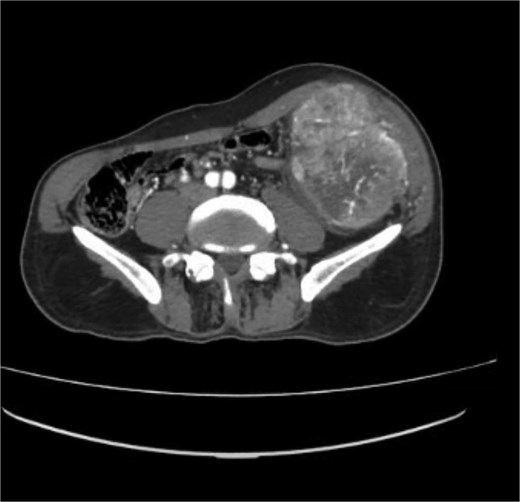

A contrast-enhanced computed tomography (CT) scan of the abdomen and chest using a triphasic protocol revealed a heterogeneously enhancing soft tissue lesion in the left iliac fossa (Fig. 1), measuring 10.8 × 9.45 cm, with central necrosis and areas of calcification. The lesion displaced adjacent intestinal loops and the left psoas muscle but did not invade these structures. Tortuous veins were observed in the subcutaneous left abdominal wall, likely representing varicose veins due to venous compression. The chest was normal.

Contrast-enhanced CT scan of the abdomen showing a heterogeneously enhancing soft tissue lesion in the left iliac fossa.